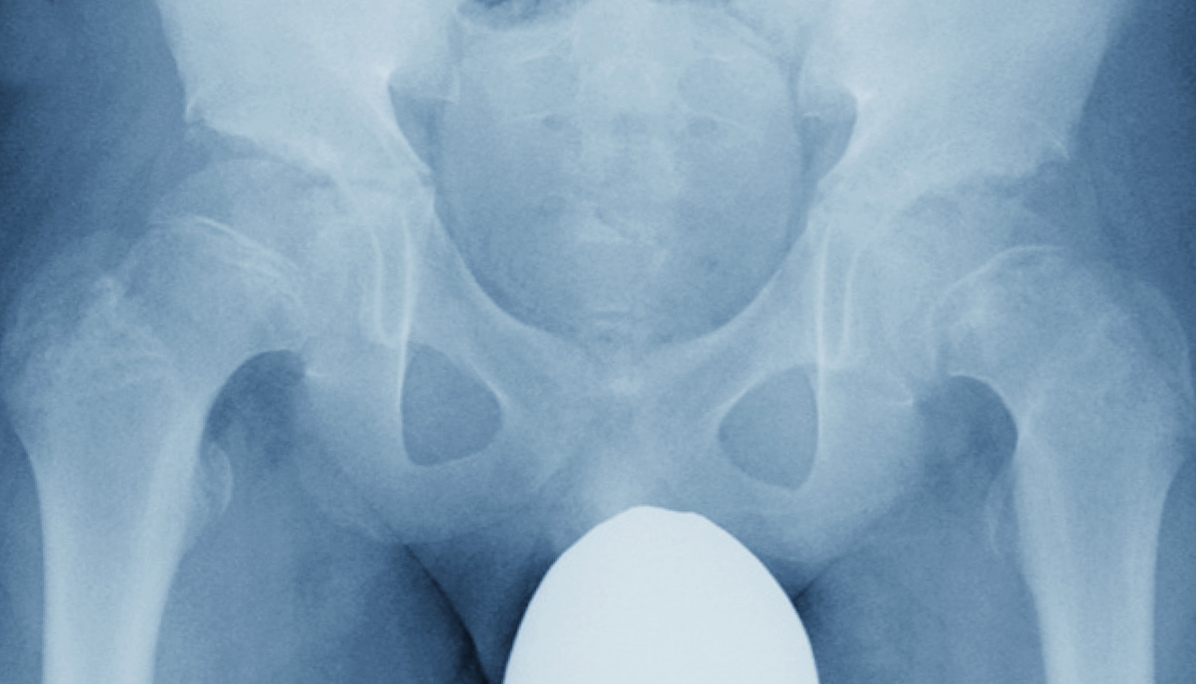

股関節は、「骨盤」と太ももの骨(大腿骨)の「骨頭」で構成されている関節です。

骨盤側はお椀のような形をしていて、そこに球状の骨頭がはまり込んでいるような構造になっています。骨盤のお椀のような形の部分を「寛骨臼」、骨頭を「大腿骨頭」と呼んでいます。

上記のようなお椀の形に球状の骨がハマり込んだ構造によって、足を開いたり曲げたり、あぐらをかいたりなどの複雑な動きを可能にしています。